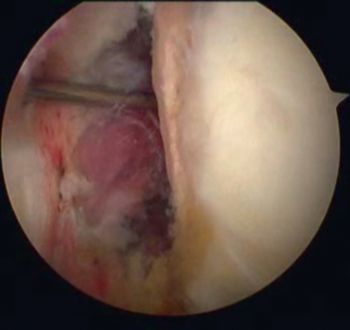

In 1985, Andrews et al. were the first to see, under arthroscopy, superior labral tears (Figure and Video) in 36 throwing athletes (sometimes associated with articular rotator cuff tears).[5]

Articular rotator cuff tears

They reported that simple debridement allowed 85% of athletes to resume their sport at the same level (Figure and Video).

Simple labral debridement

Debridement of the labrum (Video) and superficial rotator cuff tears renders varying results depending on the author, ranging from 16% for Riand et al. to 85% for Andrews et al.. Labral tears can be left repaired (Figure), rotator cuff tears should not be repaired.[45][46]